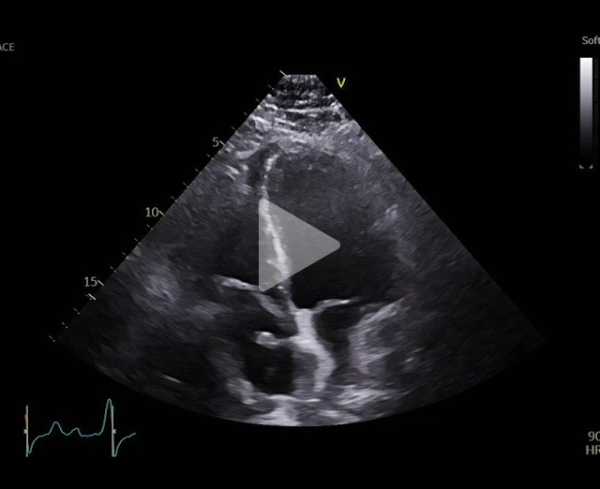

Vidéo 1

Mr T. 64 ans se présente à sa consultation de suivi cardiologique, il rapporte une dyspnée NYHA 3.

Cardiopathie dilatée d’origine ischémique à FEVG altérée (thrombus Intra VG sous Eliquis) et insuffisance rénale chronique (DFG autour de 40ml/min).

Il est entré dans la maladie avec en :

- 2009 : IDM antérieur vu tardivement avec FEVG altérée, séquelle antérieur et thrombus intra VG / Revascularisé sur l’IVA par 2 stents actifs

- 2017 : implantation CRT-D devant dégradation FEVG , BBG avec asynchronisme et dégradation VO2 —> ST Jude (loge Gauche)

- 2019 : infection de loge à SAMS , explantation puis réimplanté quelques mois plus tard devant persistance d’une dyspnée NHYA 2 se majorant

Traitement : Eliquis 5mg, Bisoprolol 10mg, Entresto 97/103mg, Eplerenone 25mg , XigDuo 5/1000mg, Inegy 10/40mg